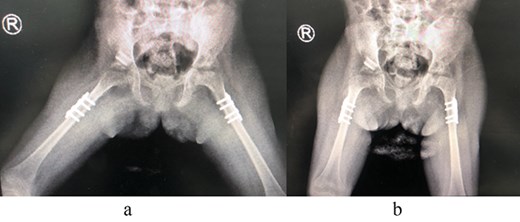

The patient underwent left hip open reduction, pelvic osteotomy, femoral shortening and hip spica followed by open reduction, pelvic osteotomy, femoral shortening and hip spica for the contralateral side six months later (Figs 2–4), the intervention was similar to regular DDH cases, no differences were noted during the surgical management. The patient was followed up closely in the clinic, and she had the implants removed after one year (Fig. 5). The patient recovered fully without any apparent postoperative complications. She was followed up in the clinic for 3 years, and she recovered fully without any complications.

(a) Post removal of implant AP view. (b) Post removal of implant lateral view.